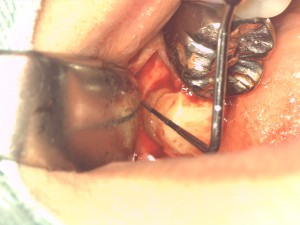

フェルールを作るために歯冠延長法を行いました。

最初に歯肉を剥離して骨の位置を確認します。骨からコンポジットレジンまでの距離は3mm

程です。

上の写真は骨を削ったところです。距離は5mmになりました。

これでクラウンの脱落は防げるしご自身の歯を長く保つことが出来るでしょう。